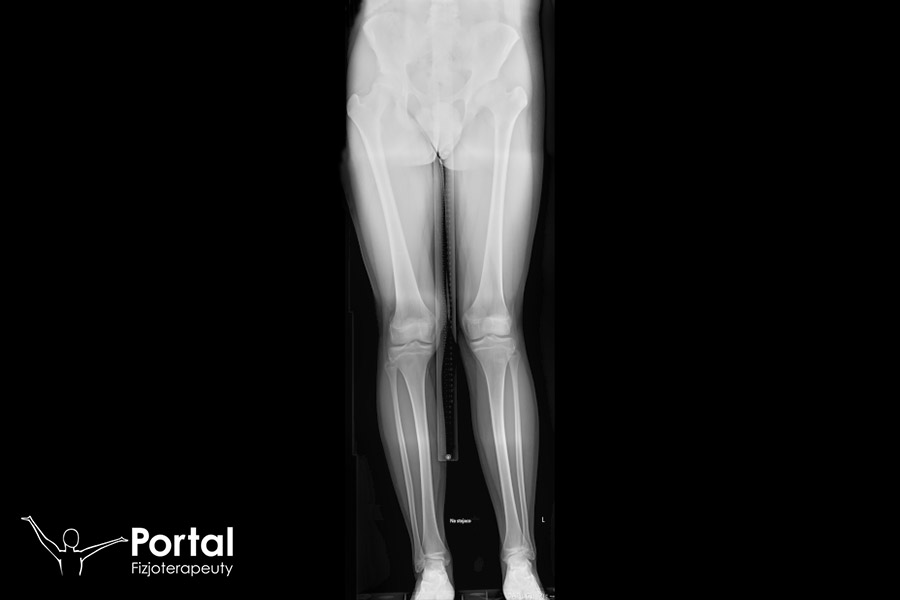

Koślawość kolana to jedna z częściej występujących wad postawy u dzieci, choć przy braku odpowiedniego leczenia może ulec utrwaleniu i towarzyszyć pacjentowi także w życiu dorosłym. W jej przebiegu oś podudzia i oś uda układają się w kąt otwarty na zewnątrz. Charakterystyczny jest odstęp powyżej 5 cm pomiędzy kostkami przyśrodkowymi lub odchylenie od osi większe niż 15 stopni.

Podstawowym objawem kolan koślawych jest przerost kłykcia wewnętrznego kości udowej oraz przeprost w stawie kolanowym, czemu towarzyszy skręcenie podudzi do zewnątrz. Zaobserwować można także skrócenie więzadła pobocznego strzałkowego oraz rozciągnięcie więzadła pobocznego piszczelowego, co znacznie zwiększa ryzyko kontuzji w obrębie kolan. Nogi układają się w kształcie litery „X”, a więc kolanami do siebie, czemu towarzyszy utworzenie się odstępu przynajmniej 5 cm pomiędzy kostkami przyśrodkowymi przy złączonych nogach. W konsekwencji tego chód staje się niezgrabny, niepewny, chwiejny. Dziecko może skarżyć się na ból i szybkie męczenie się podczas chodzenia.

Diagnostyką i leczeniem większości wad postawy zajmuje się fizjoterapeuta. Diagnostyka kolan koślawych opiera się na wykonaniu prostych testów, takich jak analiza chodu, ocena siły mięśniowej czy pomiar odległości między kostkami przyśrodkowymi. Niektórzy specjaliści rekomendują dodatkowe wykonanie RTG, szczególnie wtedy, gdy istnieje podejrzenie anomalii kostnych lub urazów.